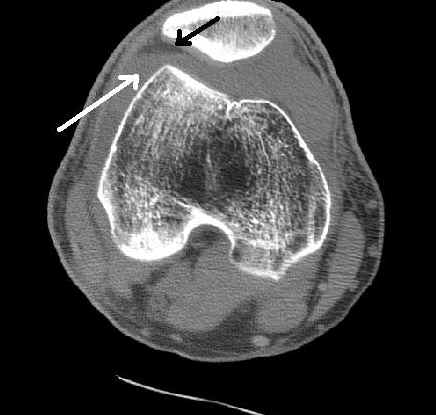

This axial CT demonstrates the lipohemarthrosis in the patellofemoral compartment of the knee. The black arrow demonstrates the fat while the white arrow demonstrates blood.